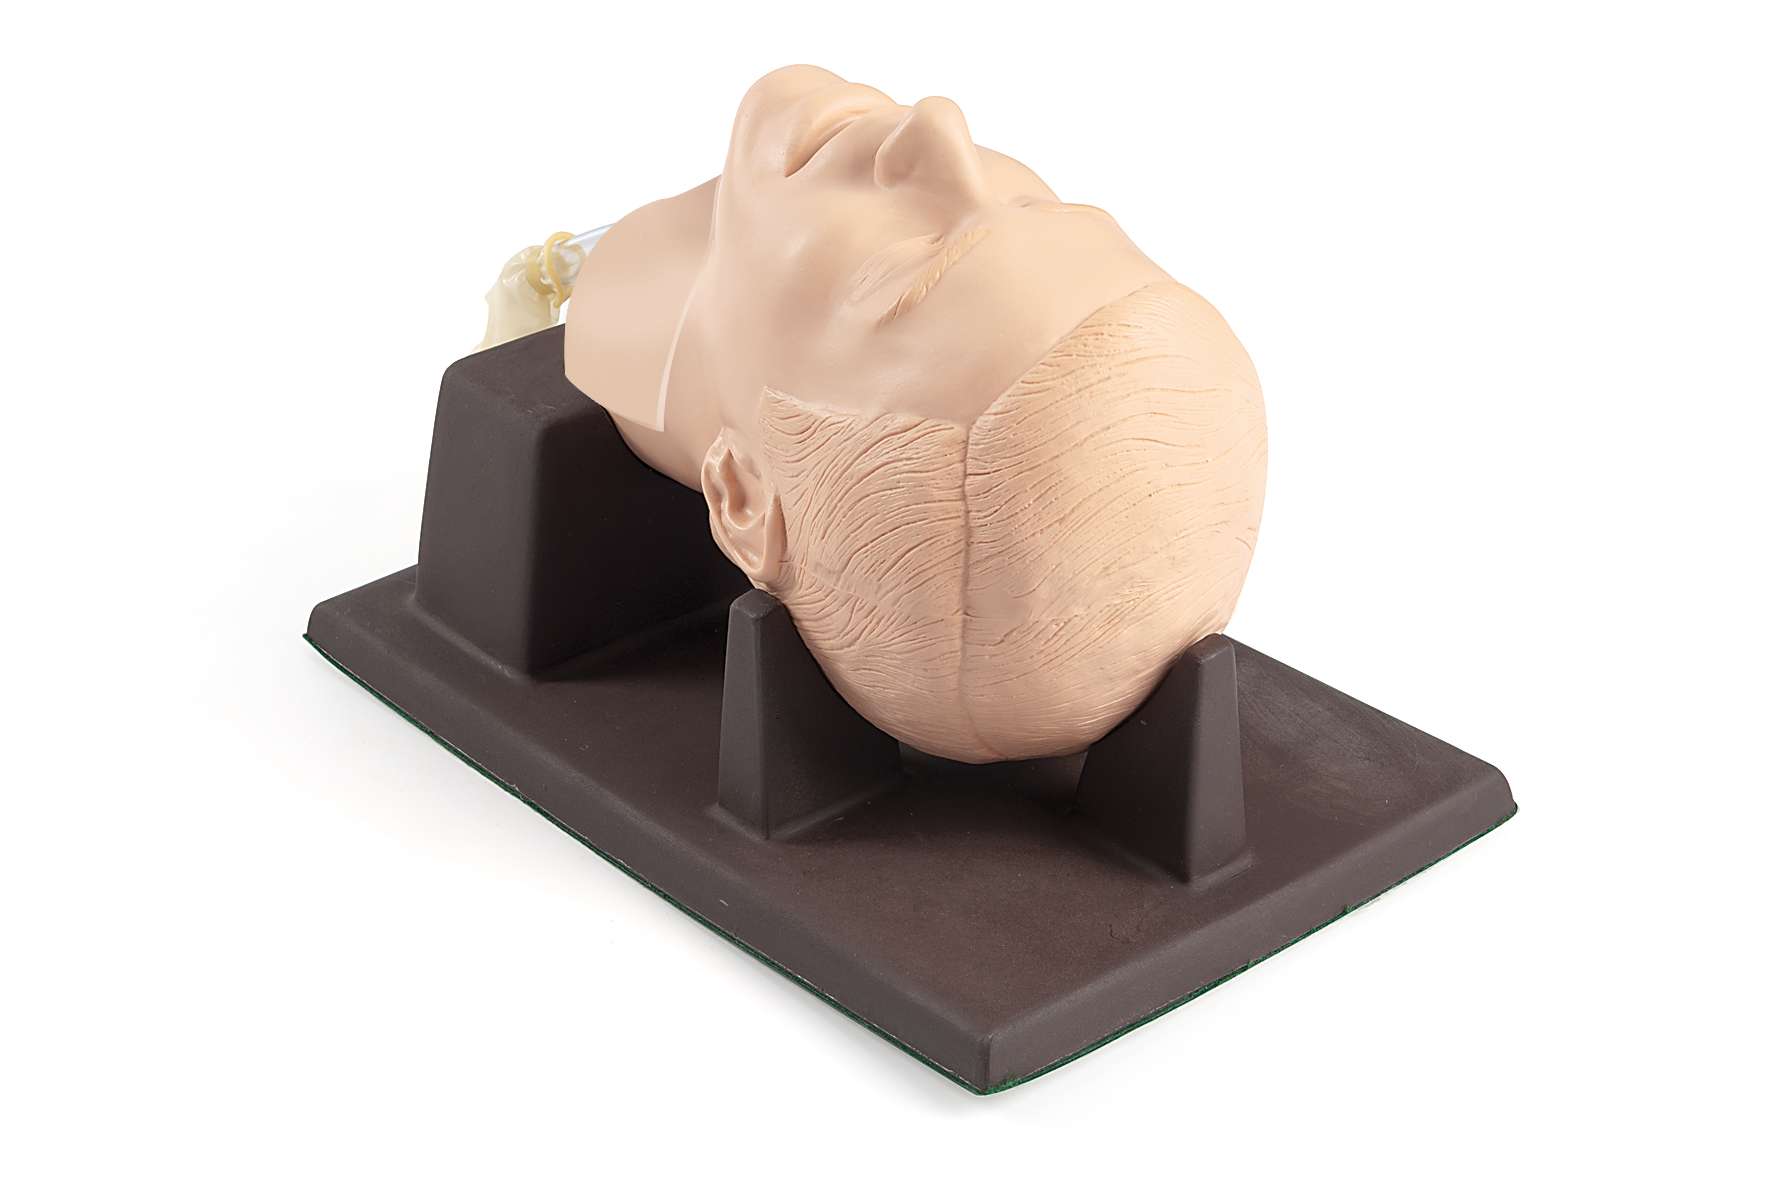

Nuestros maniquíes médicos vienen en varias formas, incluidos maniquíes para adultos , maniquíes de simulación neonatal y maniquíes de simulación pediátrica , para apoyar la capacitación en RCP, primeros auxilios y habilidades clínicas avanzadas. Estos maniquíes médicos son esenciales para simular situaciones de emergencia y permitir que los estudiantes practiquen técnicas para salvar vidas en un entorno seguro y controlado.

Los simuladores de pacientes son una parte integral de nuestro equipo de simulación y capacitación , que ofrece una experiencia realista al replicar ritmos cardíacos, problemas respiratorios y lesiones. Estos simuladores son invaluables para la simulación de atención de emergencia , simulación de cuidados críticos y simulación de traumatismos , lo que garantiza que los profesionales de la salud estén preparados para emergencias médicas del mundo real. Nuestros productos de simulación de atención médica brindan un aprendizaje inmersivo, lo que permite la capacitación en todo, desde procedimientos médicos básicos hasta técnicas quirúrgicas complejas.